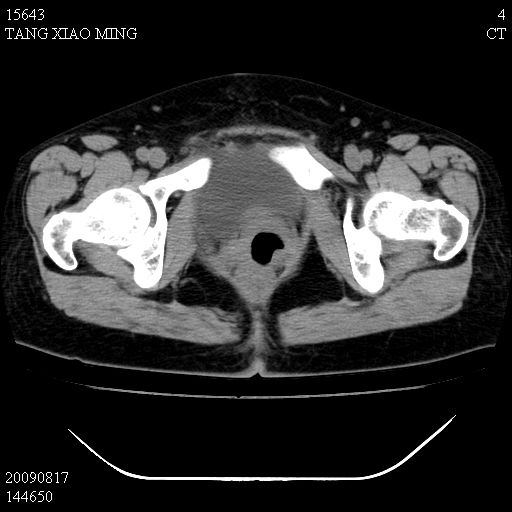

标题: CT21692:盆腔病变

女,33岁,右下腹痛2年余,既往宫外孕病史,如在我院手术,结果下周公布,

可能的诊断。1子宫内膜异位【子宫腺肌症并右卵巢巧克力囊肿】;2 右卵巢囊腺瘤。子宫肌瘤

1)考虑卵巢巧克力囊肿,不排除卵巢囊腺瘤。2)子宫肌瘤可能。

卵巢囊腺瘤,子宫肌瘤,直肠壁厚,不除外占位.